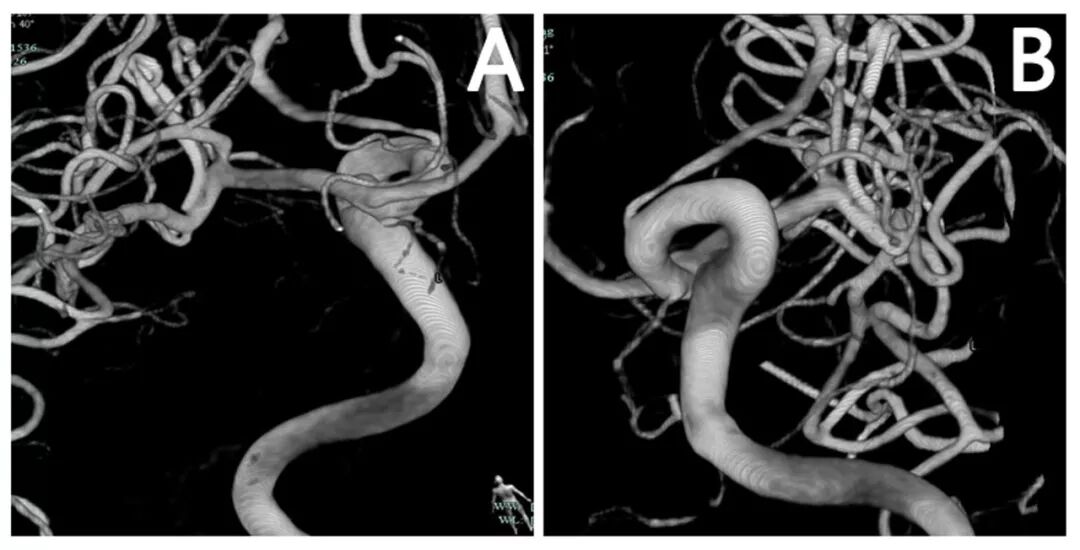

图3. 患者手术后复查全脑DSA情况。3D-DSA提示动脉瘤完全夹闭,瘤夹位置理想,M1载瘤血管及分叉部颞前动脉和M2主干血流通畅。

图6. 患者手术后复查全脑DSA情况。3D-DSA提示动脉瘤完全夹闭,瘤夹位置理想,M1载瘤血管及分叉部颞前动脉和M2主干血流通畅。